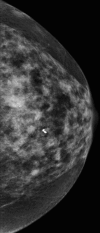

Paraneoplastic polymyositis presenting as a clinically occult breast cancer

Paraneoplastic syndrome affects less than 1% of cancer patients. Diagnosis of paraneoplastic syndrome with neurological presentation requires screening for an underlying malignancy, including a complete history, physical examination and imaging studies. Treatment often results in symptom stability, rather than improvement. Paraneoplastic polymyositis can precede or instantaneously occur at diagnosis or treatment of a primary tumour, while neurological symptoms can persist even following cancer treatment. We report a rare case of metaplastic breast carcinoma with an unusual presentation of paraneoplastic polymyositis.